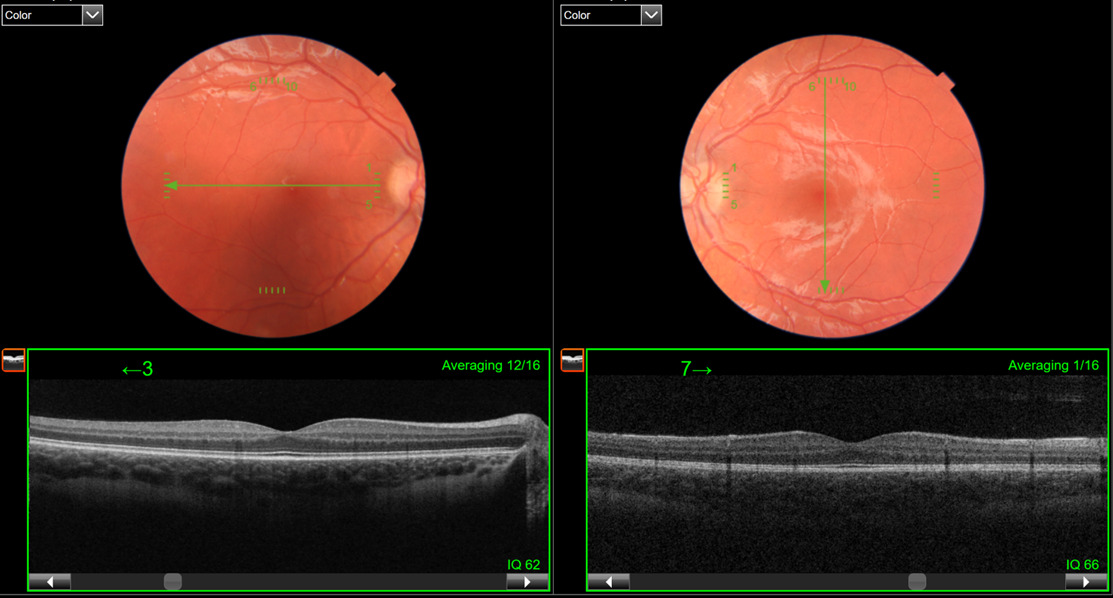

A 14-year-old male patient presented for a comprehensive visual assessment to determine driving eligibility. He had been informed previously that he had reduced vision but could not recall if he had a formal diagnosis of amblyopia when questioned. He reported a positive ocular history for nystagmus, which had been present since birth, and noted current headaches in his review of systems. Personal health history was otherwise unremarkable. He reported full-time spectacle wear for several years, without prior history of patching, atropine, or vision therapy. The habitual spectacle prescription was +3.00 -5.25 x 175 and +1.75 -3.25 x 006, with entering and best-corrected visual acuities of 20/70 and 20/60- in the right and left eyes, respectively, with single letters surrounded by crowding bars and a frosted lens over the contralateral eye. Cover test revealed a high magnitude, nearly constant alternating exotropia. Although extraocular muscles had a full range of motion, he had a horizontal jerk nystagmus, with exacerbation of amplitude in left gaze and dampening in right gaze. There was a latent component to the nystagmus, which was worse in the right eye. Near point of convergence was attempted but unmeasurable, and there was no measurable contour or random dot stereopsis as tested by the stereo fly, Randot Butterfly, or Wirt Rings. Further fusion findings, including Worth Dot, are listed in Table 1. External ocular health was unremarkable, with no transillumination defects of the iris, but the patient had light blonde hair, fair skin, and blue irises. A dilated posterior segment evaluation showed a blonde fundus with no foveal reflex, and a 5-line raster optical coherence tomography scan confirmed grade 3 foveal hypoplasia in both eyes (see Figure 1).

Figure 1

Figure 1.5-line raster optical coherence tomography scans of the right and left eye, demonstrating grade 3 foveal hypoplasia in each eye.